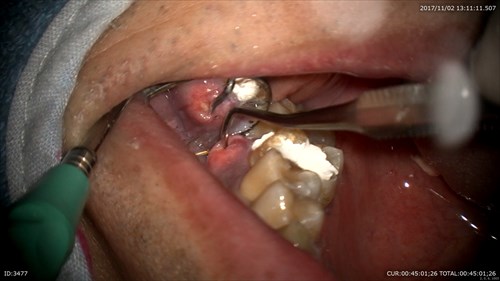

3ケース目 他院からいらっしゃった方です。腫れが引かない。

根管見えにくいですね。

マイクロで探します。重症のむし歯は皆さんこんなになっています。感染源が取れていないだけの様です。